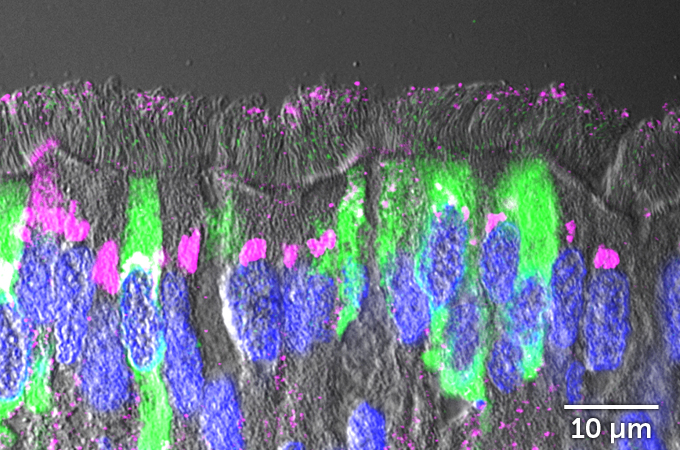

But not all the cells in the infected lawn were affected equally. Looking at the cells from the side, researchers could see that cells sporting cilia were infected with the coronavirus. But mucus-producing cells called goblet cells, which don’t have cilia, were rarely infected. That may be because a protein called ACE2 decorates the surface of ciliated cells far more often than it does goblet cells. ACE2 is the protein that the coronavirus uses as a door into cells.

Counting cells under the microscope, the researchers saw that far fewer of the infected cells treated with IL-13 got the heave-ho. Whereas the untreated cells had ejected about 700 of their own by about four days after infection, only about 100 treated cells had gotten kicked out. The images showed that IL-13 really was protecting cells from infection. But how was still an unanswered question.

One thing that IL-13 does is stimulate airway-lining cells to churn out a type of sticky mucus that can trap viruses before they can infect cells. The team found that untreated cells released a burst of the mucus shortly after being infected with the coronavirus, depleting stores of the sticky stuff. But cells treated with IL-13 were still well-stocked with mucus.

Examining patterns of gene activity, the team found that IL-13 was also causing cells to make less ACE2, the protein that SARS-CoV-2 commandeers as a gateway into cells. “It makes it much harder for the virus to find its door to enter the cells,” Ehre says.

Cells treated with IL-13 also turn down the activity of genes involved in making protein-producing factories called ribosomes, the researchers discovered. That may limit viral replication in cells. But some genes’ activity was also turned way up. That includes several genes involved in making keratan sulfate, a long chain of sugars that is found in cartilage and the eyes’ corneas. “It’s there in the body to make a shield,” Ehre says.

That seems to be what it is doing for airway cells too. A thick layer of keratan sulfate developed on top of cells treated with IL-13, armoring them against a coronavirus infection.